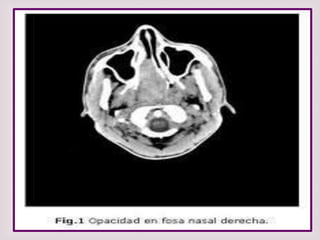

EXÁMENES RADIOGRÁFICO

RX SENOS PARANASALES

De poca ayuda en el dx de pólipos

nasales altos falsos positivos y falsos

negativos.

TUMOGRAFIA COMPUTADA TC

Para confirmar localización y

extensión de la lesión. De gran

utilidad permite planear tipo de

cirugía y evitar complicaciones .

POLIPO NASAL